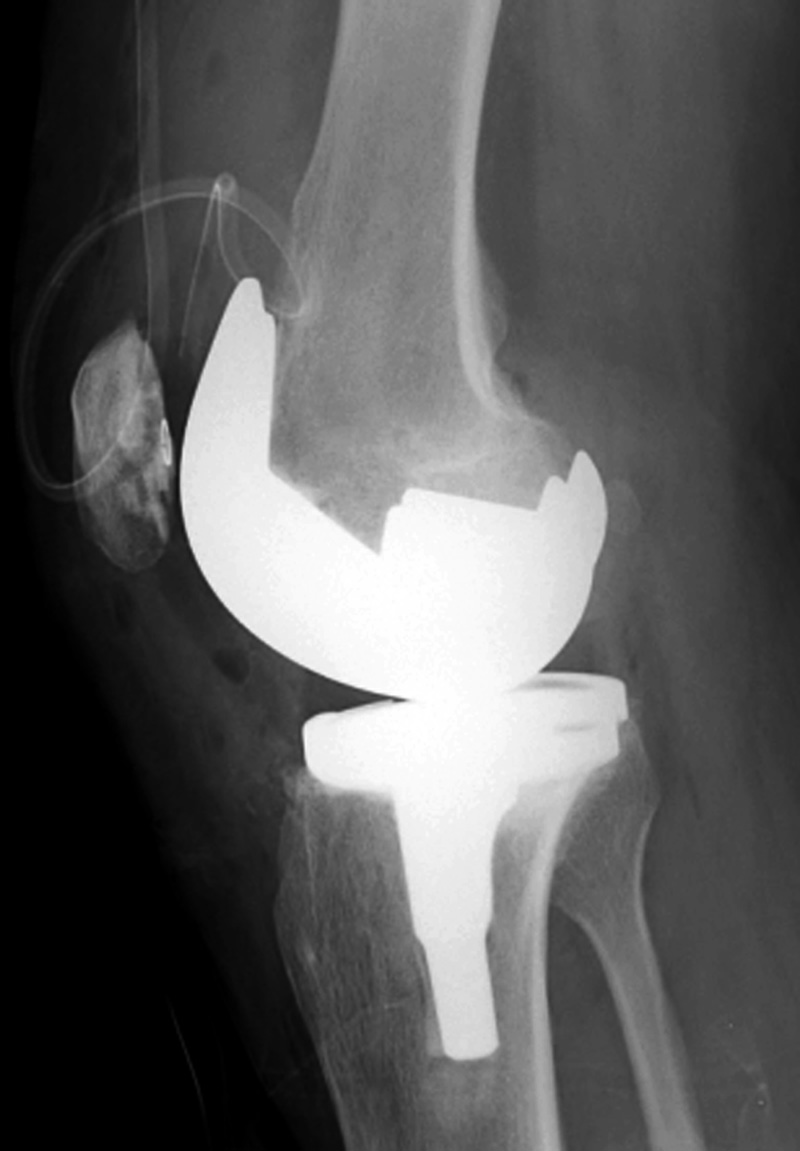

Rotating-hinge knee implants provide a mechanical linkage between the

femoral and tibial components and are used in

revision and tumor surgery when the bone and

soft tissues about the knee are severely damaged. These are highly constrained devices (figure: rotating-hinge knee implant; figure: rotating-hinge knee implant with failure). The tibial and femoral components are linked via a hinge which considerably limits varus-valgus and translational movement. The knee can only rotate approximately 10 degrees from flexion to extension (Mulcahy, 2013). Other variations on total knee arthroplasty designs have been introduced including a medial pivot knee design and a high flexion knee design.

| Biomet XPA Bicruciate Preserving total knee arthroplasty |

| 67 year-old woman. A surgical drain is present from recent surgery. From Taljanovic, 2005 |